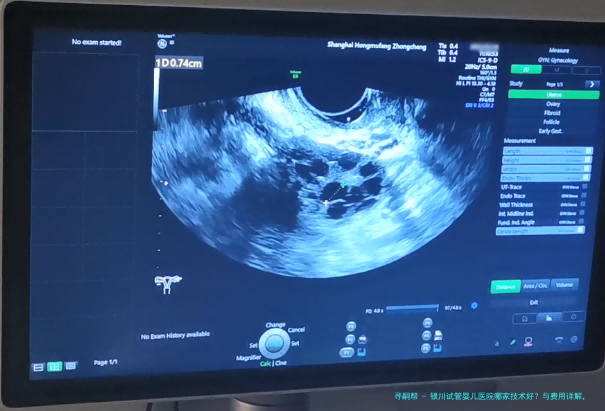

是动态数据,受患者岁数、病因、胚胎质量等多要点影响。银川主要生殖医学中心的临床妊娠率(移植后经B超认定怀孕的比率)在40-55之间,符合国内平均水平。宁夏医科大学总医院银川市妇幼保健院因其例子量大、技术安定,统计常处在地区前线。但务必理解,是统计观点,个体情况需详细解析。

孕期早期监测(B超等)1500//td>8001100900-1300